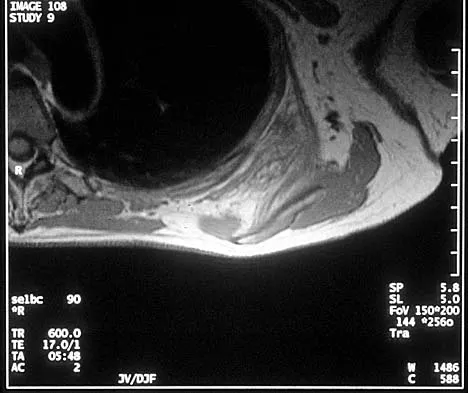

Figure 42 shows the sagittal T2-weighted MRI scan of a patient's right knee. These findings are most commonly seen with a complete tear of the

The MRI scan reveals disruption of the lateral capsule and ligaments with fluid in the soft tissues laterally. Additionally, there is a large bone bruise on the medial femoral condyle. This combination indicates injury to the posterolateral complex. These injuries often have coexisting anterior and/or posterior cruciate ligament injuries. Failure to recognize the posterolateral corner injury can lead to failure of anterior or posterior cruciate ligament reconstructions. LaPrade RF, Gilbert TJ, Bollom TS, et al: The magnetic resonance imaging appearance of individual structures of the posterolateral knee: A prospective study of normal knees and knees with surgically verified grade III injuries. Am J Sports Med 2000;28:191-199.